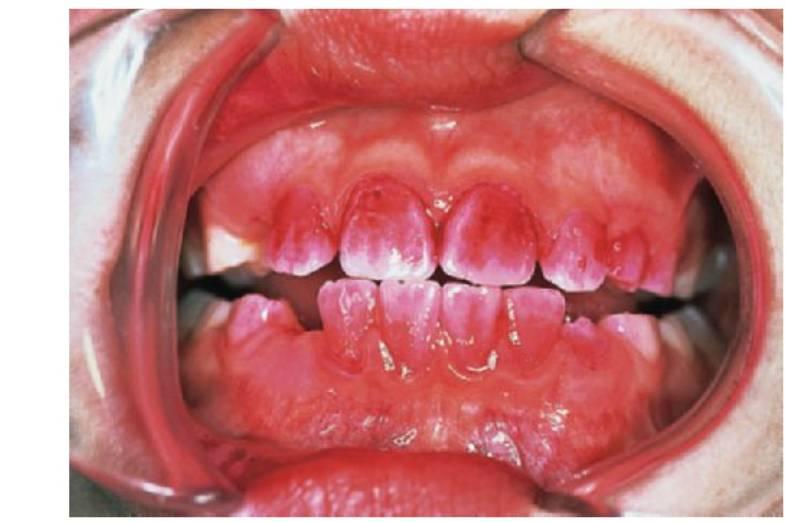

Características de las caries inducidas por el biberón en la infancia temprana

- Las caries rampantes afectan a los dientes anterosuperiores (fig. 3.5).

- Las lesiones aparecen después en los dientes posteriores, los primeros molares maxilares y mandibulares.

- Los caninos están menos afectados que los primeros molares porque erupcionan después.

- Los dientes anteroinferiores no están afectados, se supone que debido al flujo salival y a la posición de la lengua.

- El biberón suele utilizarse como chupete para conseguir que el niño se duerma.

- Las caries de biberón se presentan en todos los grupos socioeconómicos y suelen reflejar la dinámica social de la familia. Los niños que duermen mal o tienen cólicos suelen tranquilizarse con el biberón. El biberón puede contener cualquier líquido con carbohidratos fermentables, incluso leche, si bien suelen usarse con bebidas y zumos que con tienen vitamina C.

- Este patrón de caries puede presentarse también a partir de una lactancia materna a demanda prolongada.